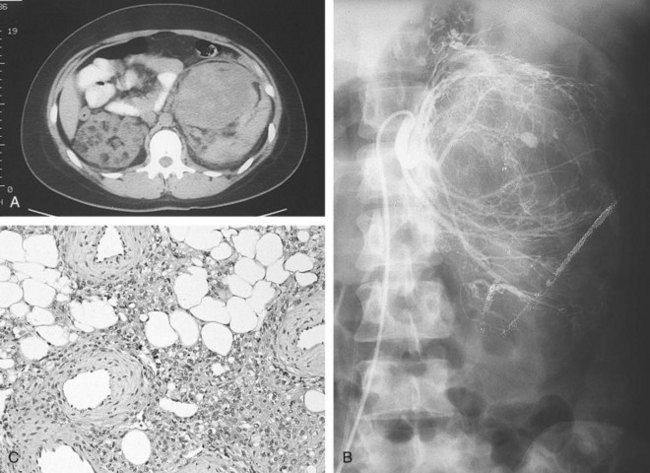

Angiomyolipoma is the only benign renal tumor that is confidently diagnosed on cross-sectional imaging (Fig. 51–7). The presence of fat (confirmed on nonenhanced thin-cut CT by a value of −20 Hounsfield Units [HU] or less) within a renal lesion is considered the diagnostic hallmark (Jinzaki et al, 1997; Lemaitre et al, 1997; Bosniak et al, 1998; Simpfendorfer et al, 2009). Findings of more than 20 pixels with attenuation less than −20 HU and of more than 5 pixels with attenuation less than −30 HU have been shown to have a positive predictive value of 100% (Simpfendorfer et al, 2009). Ultrasonography shows a well-circumscribed, highly echogenic lesion with shadowing (Siegel et al, 1996; Lemaitre et al, 1997). On angiography (or CT-angiography) aneurysmal dilation is found in 50% of angiomyolipomas (Lemaitre et al, 1997). The size of the aneurysms has been reported to correlate with the risk of rupture (Yamakado et al, 2002). MRI can be used in difficult cases or in lieu of CT, with findings on fat-suppressed images being highly suggestive of the diagnosis.

Figure 51–7 A, CT scan demonstrating large bilateral renal angiomyolipomas in a patient with tuberous sclerosis. B, Renal angiogram shows increased vascularity and aneurysmal dilation characteristic of angiomyolipoma. C, Typical microscopic appearance of angiomyolipoma with admixture of mature adipose tissue, smooth muscle, and thick-walled blood vessels.